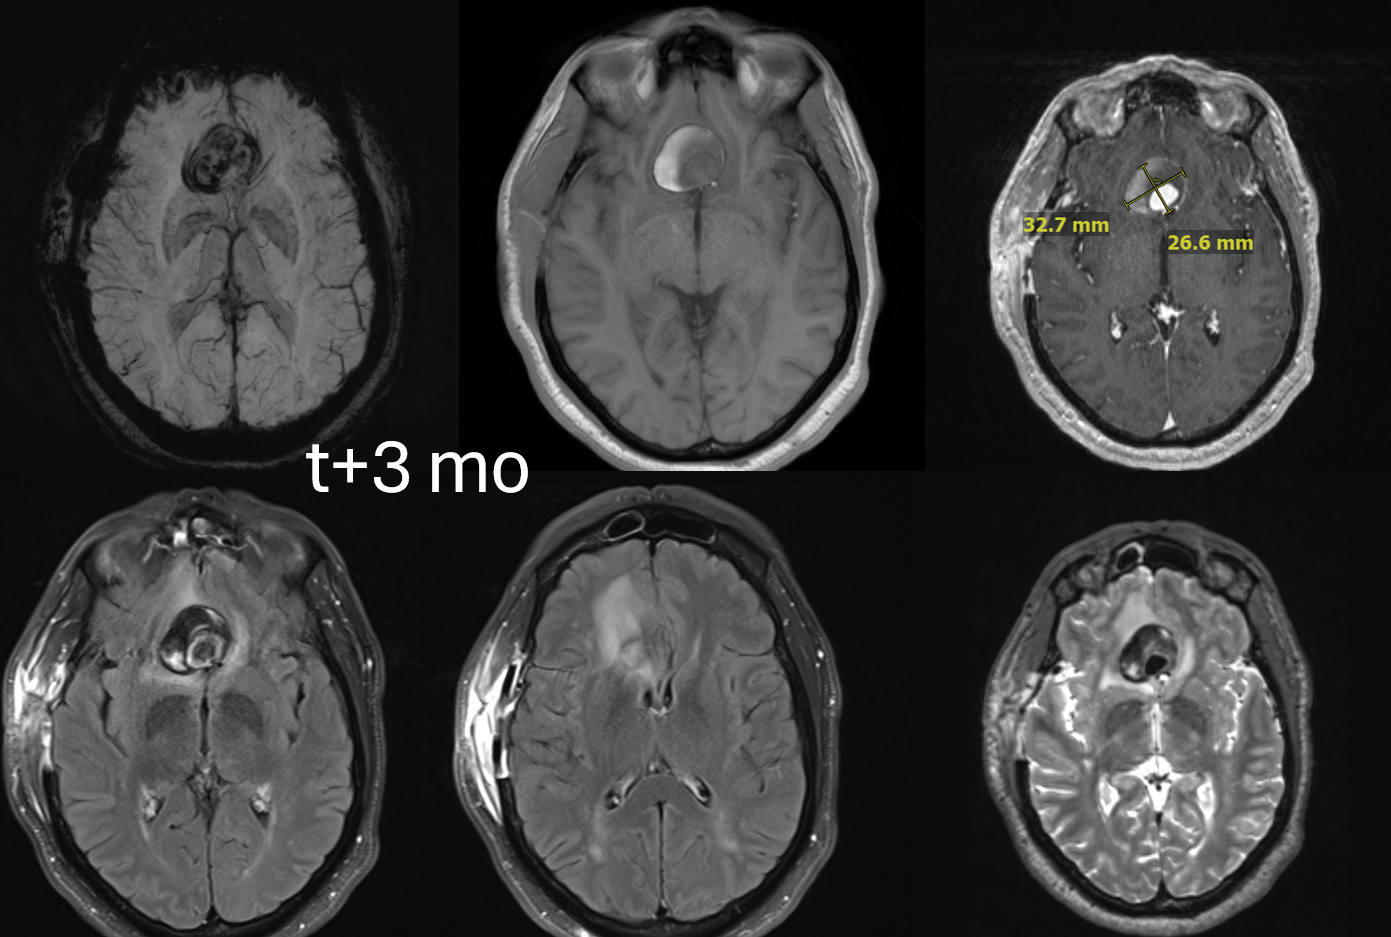

One month later — only 1 mo. Aneurysm thrombosed. Right A1-A2 patent — can tell on MRA even with two SVBs

Several months later, MRI looks fantastic — no edema, smaller, etc. This MRI is actually enough to know the aneurysm is gone. Its more sure than angio.

MRA